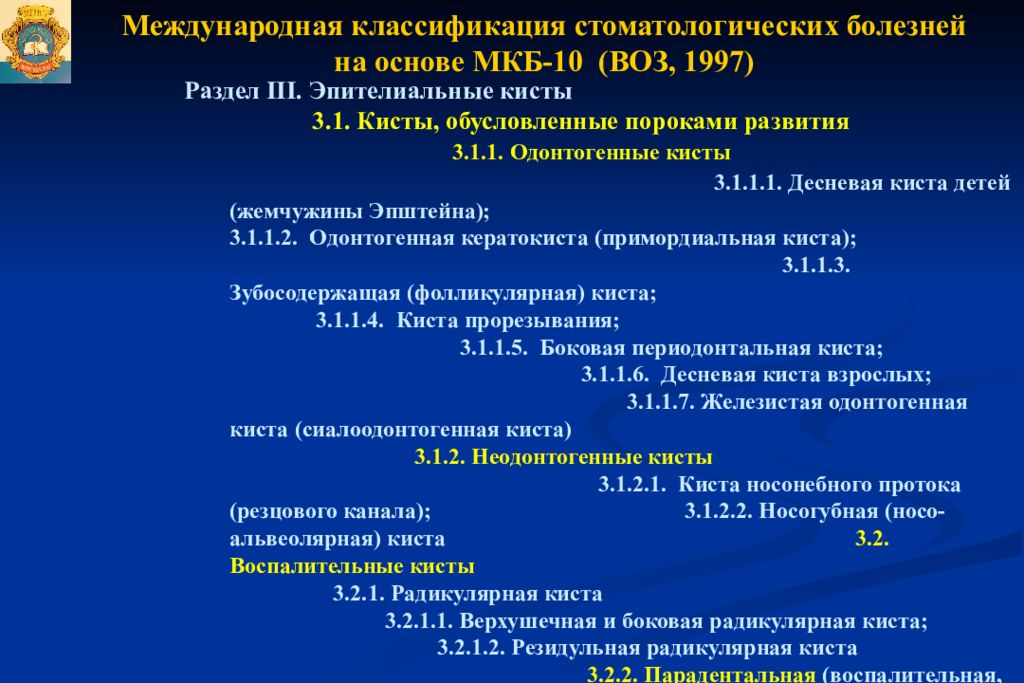

Код мкб 10 атерома головы

Код мкб 10 атерома головы 109 фото